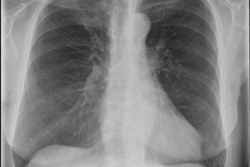

A retrospective study of almost 39,000 patients shows that opportunities to diagnose chronic obstructive pulmonary disease (COPD) at an earlier stage are frequently being missed in both primary and secondary care in the U.K.

The findings, published online on 13 February in the Lancet Respiratory Medicine, found that the missed COPD diagnoses occurred in up to 85% of people.

Study author Dr. Rupert Jones from Plymouth University Peninsula said the substantial numbers of patients misdiagnosed and underdiagnosed is a cause for concern. Early diagnosis of COPD can lead to more effective treatment and reduce lung damage and improve quality of life and life expectancy.